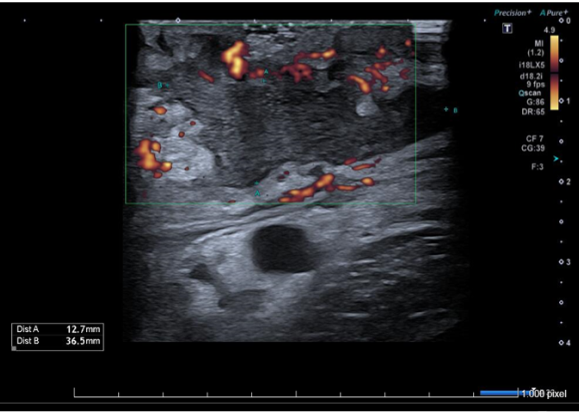

Ecografía de partes blandas de axila izquierda: Piel engrosada con aspecto hipoecogénico y heterogéneo. Tejido celular subcutáneo con cambios inflamatorios y edema, que simula imagen en forma de nubes. Colección de 13x36 mm en tejido celular subcutáneo con márgenes irregulares, contenido ecogénico fluctuante con trazos hiperecogénicos periféricos. Vasos regionales permeables sin signos de trombosis. Hallazgos compatibles con absceso subcutáneo y celulitis.

En el caso de colecciones permite identificar sus características: el tipo de contenido (sólido/líquido), el contorno, la vascularización y la presencia de septos o tabiques. Por otro lado, mejora la toma de decisiones terapéuticas y aumenta la seguridad del drenaje, en caso de ser preciso, al servir de guía durante el procedimiento permitiendo evitar estructuras vasculares y nerviosas.